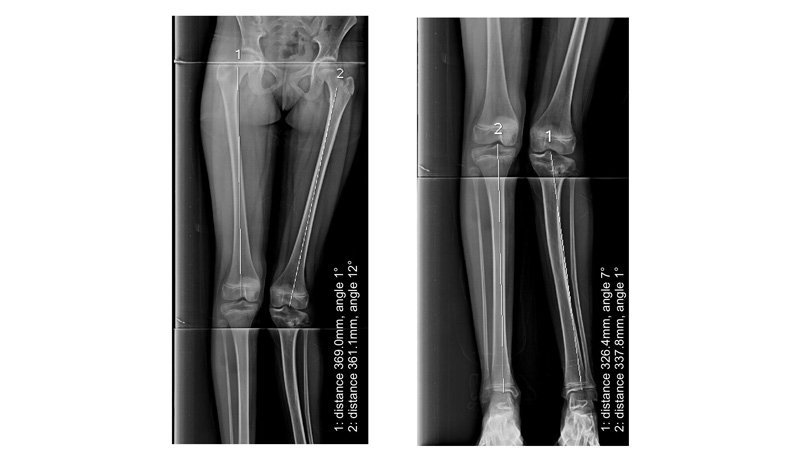

1 : For planning of any realignment operation of lower limb, mainly for genu valgus & varus deformity due to osteoarthritis / post # healing. 2 : To measure limb length discrepancy - congenital/acquired. 3 : For evaluation of kyphoscoliosis spinal dysraphism or identification of curve apex, end vertebra, neutral vertebra, stable vertebra, major V/S minor curves, structural V/S non-structural curves.